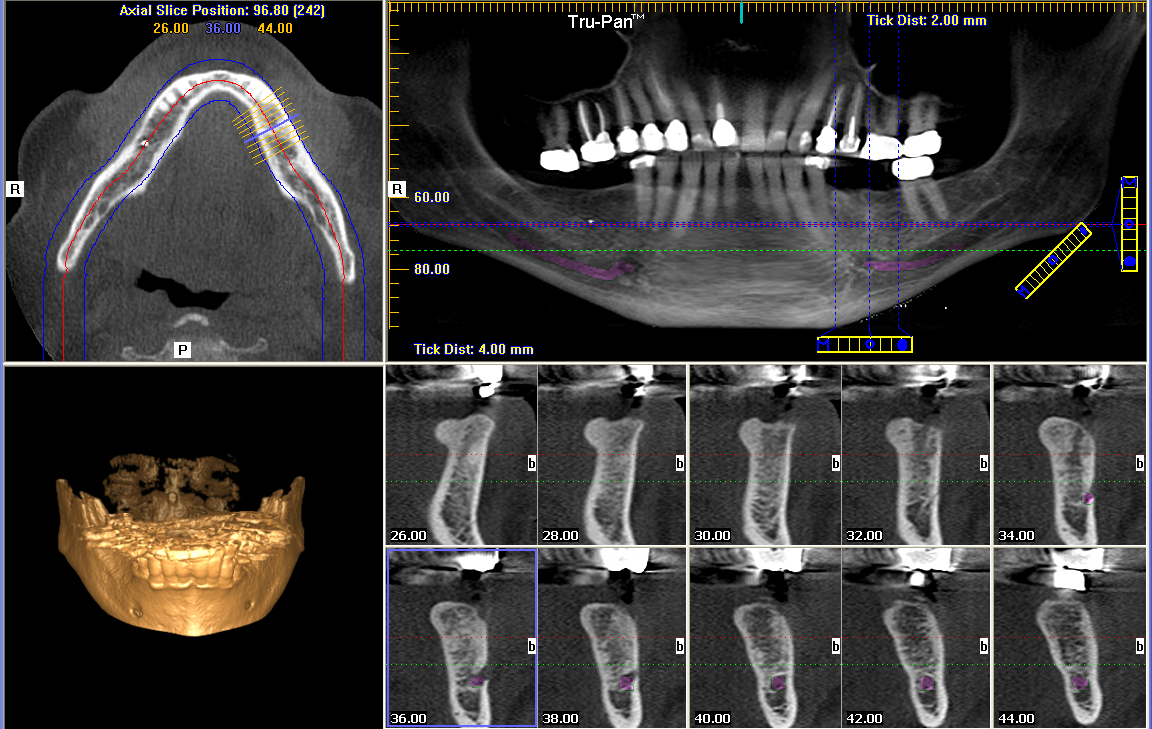

Tomografia Computadorizada Cone Beam Para Iniciantes - Blog Radio

blog.radiomemory.com.brTomografia Odontológica Preço – RadioCenter Curitiba

blog.radiomemory.com.brTomografia Odontológica Preço – RadioCenter Curitiba